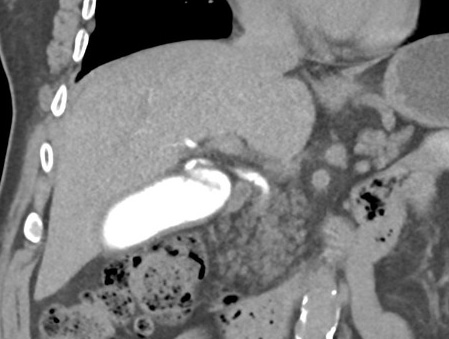

| |

Image TDM de l'abdomen en

coupe coronale ( frontale)apres recontruction

saciale avec contrast iode . La vesicule biliaire

est en vue |

|

Aspect normale de la

vesicule biliaire et de la veine

porte commun en coupe TDM coronale . |